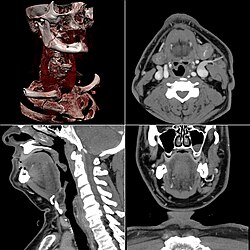

Kombination aus multiplanarer Reformatierung und sliding thin slab. Der Bildkursor befindet sich in der Harnblase. Die Originalschichtdicke beträgt 1,25 mm, dargestellt wird in allen Ansichten gemittelt (= average) in 3,7 mm bzw. 3,8 mm Dicke. -